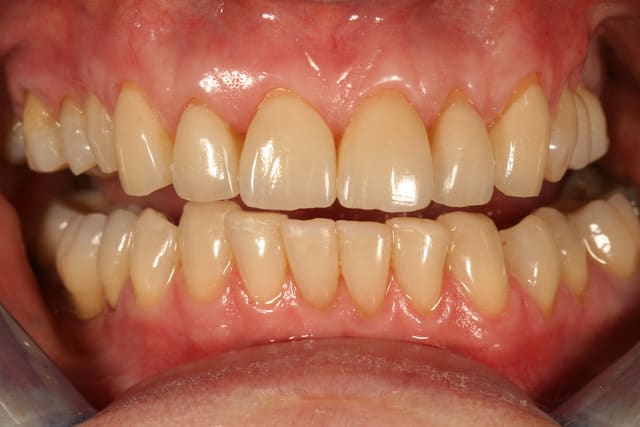

enfin un cas sympa pour faire des facettes, et a part une unitaire une fois c'est mon premier cas

le premier mock up était tout penché un peu plat, j'ai rajouté du composite par dessus la cire pour en faire un second qui nous plaise plus, à la patiente et à moi.

on a pas voulu toucher le collet de la 12, patiente pas motivée pour chir et ça me simplifiait la vie pour une première

ce sont des emax qui sont prévues